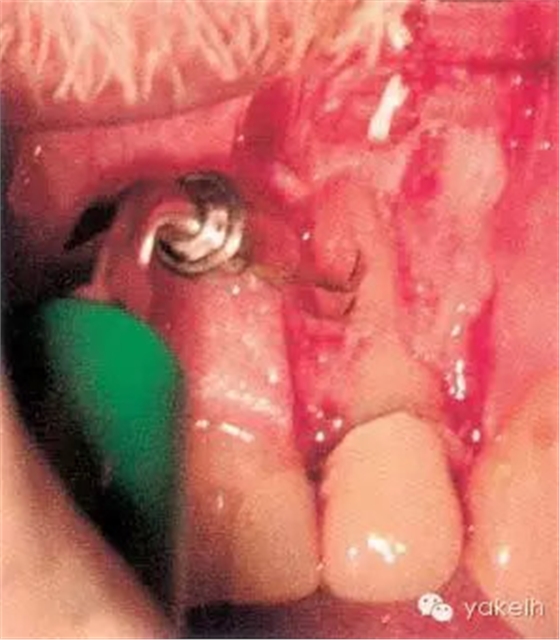

¤¤在征得患者同意后,最終選擇根管外科手術(shù)修復(fù)穿孔。局麻下翻開三角形全厚黏骨膜瓣,充分暴露骨和根面;使用刮匙去除穿孔上覆蓋的肉芽組織,暴露穿孔和樁(圖5.4.2a);使用外科專用渦輪手機配以金剛砂小球鉆,去除樁的尖端;使用超聲銼去除根管末端的牙膠,并進行根管預(yù)備(圖5.4.2b);預(yù)備后的根管與穿孔部位使用IRM嚴密封閉(圖5.4.2c);瓣復(fù)位、縫合固定,拍攝術(shù)后X線片(圖5.4.3a);3天后拆線。

圖5.4.2(a)去除肉芽組織,暴露穿孔和樁。